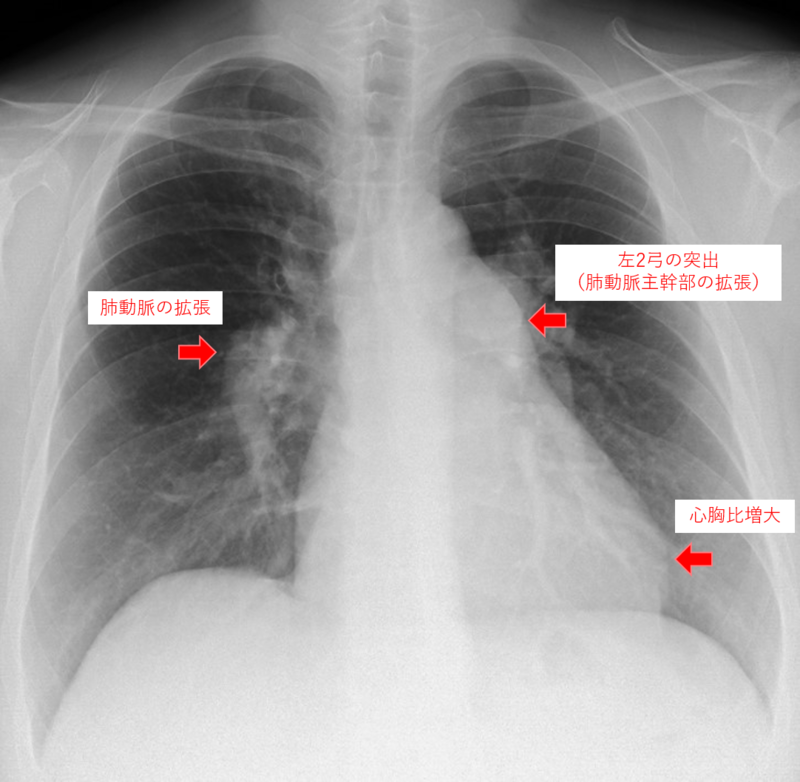

こちらは肺高血圧症患者さんの胸部レントゲン画像です。肺高血圧症による肺動脈および右心室・右心房の拡張による変化がみられます(矢印部分)。